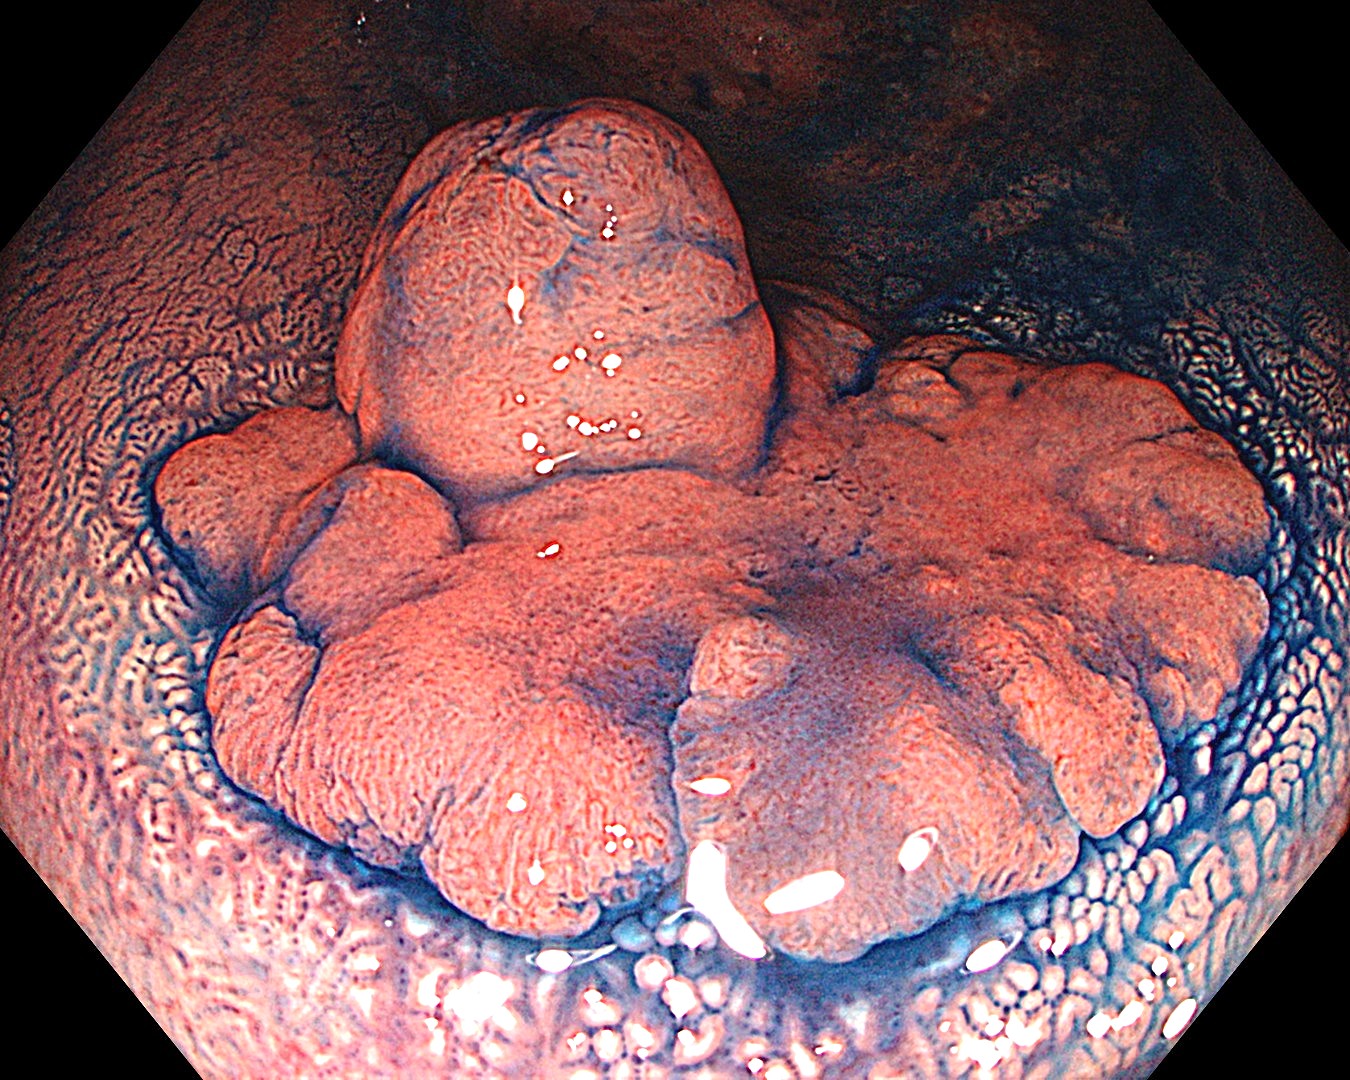

• 白色光観察①(中遠景)

強調設定:A8

図1

白色光観察で、下部直腸に20mm大の境界明瞭で発赤調の隆起性病変を認めた。病変は、丈の高い隆起部と平坦隆起部からなる 0-Is+IIa病変として認識された。周囲粘膜に白斑を伴っており、腺腫~大腸癌が疑われた。